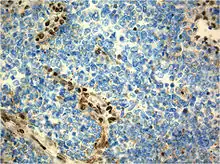

Immunohistochemistry

Immunohistochemical staining is widely used in the diagnosis and treatment of cancer. Specific molecular markers are characteristic of particular cancer types. Immunohistochemistry is also widely used in basic research to understand the distribution and localization of biomarkers in different parts of a tissue. Proteins found in an ATeratoid/RT are:

- Vimentin-positive

- Cytokeratin-positive

- Neuron specific enolase-positive

- Epitelial membrane antigen-positive

- Glial fibrillary acidic protein- positive

- Synaptophysin

- Chromogranin

- Smooth muscle actin

- Desmin

- Carcinoembrionary antigen

- CD99 antigen;[19][20]

- S-100

- neurofilaments

- AFP – not found

- HCG – negative